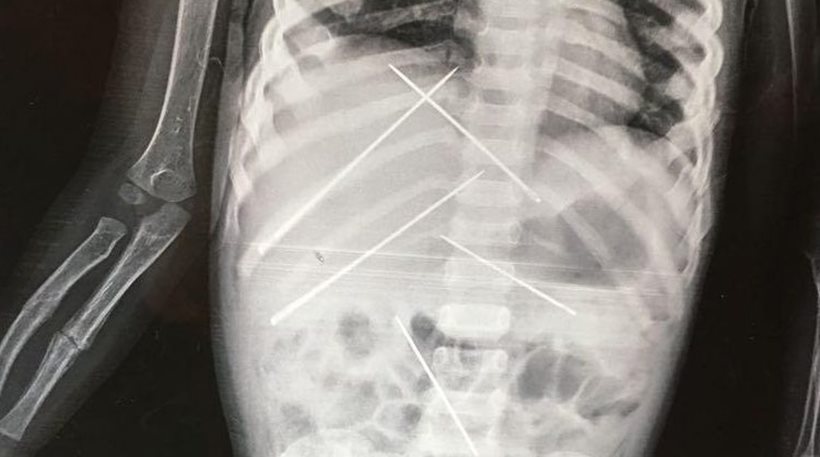

Βρίσκονταν μέσα της για τουλάχιστον 15-20 ημέρες, ενώ είχε και σπασμένο χέρι – Σοκ στους γιατρούς από την ακτινογραφία – Συνελήφθη ένας 50χρονος άνδρας

Όταν υποβλήθηκε σε ακτινογραφία, οι γιατροί αντίκρισαν ένα πρωτοφανές θέαμα. Σχεδόν 10 μεγάλες βελόνες είχαν καρφωθεί μέσα στο σώμα του 3χρονου κοριτσιού, σε διάφορα σημεία. Επίσης, το ένα χέρι του παιδιού ήταν σπασμένο.